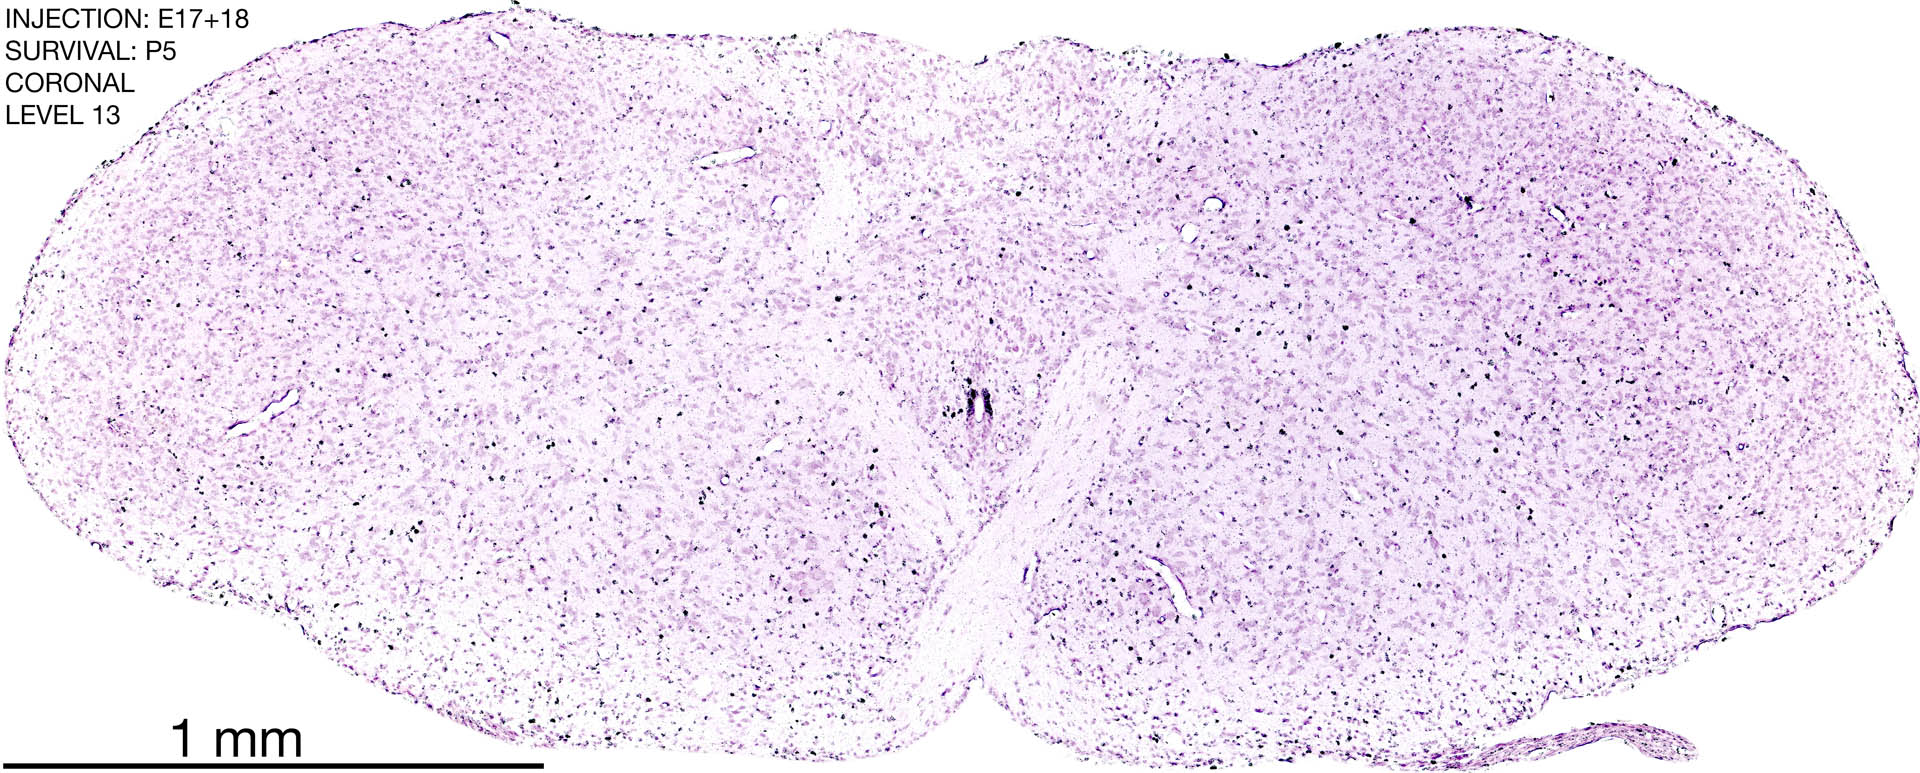

E17+18 P5 Survival The images below are from the brain of a rat that was exposed to tritiated thymidine on E17+18 and survived to P5. Download: Large | High Res Download: Large | High Res Download: Large | High Res Download: Large | High Res Download: Large | High Res Download: Large | High Res Download: Large | High Res Download: Large | High Res Download: Large | High Res Download: Large | High Res Download: Large | High Res Download: Large | High Res Download: Large | High Res Download: Large | High Res Download: Large | High Res Download: Large | High Res Download: Large | High Res Download: Large | High Res Download: Large | High Res Download: Large | High Res Download: Large | High Res Download: Large | High Res Download: Large | High Res Download: Large | High Res Download: Large | High Res Download: Large | High Res